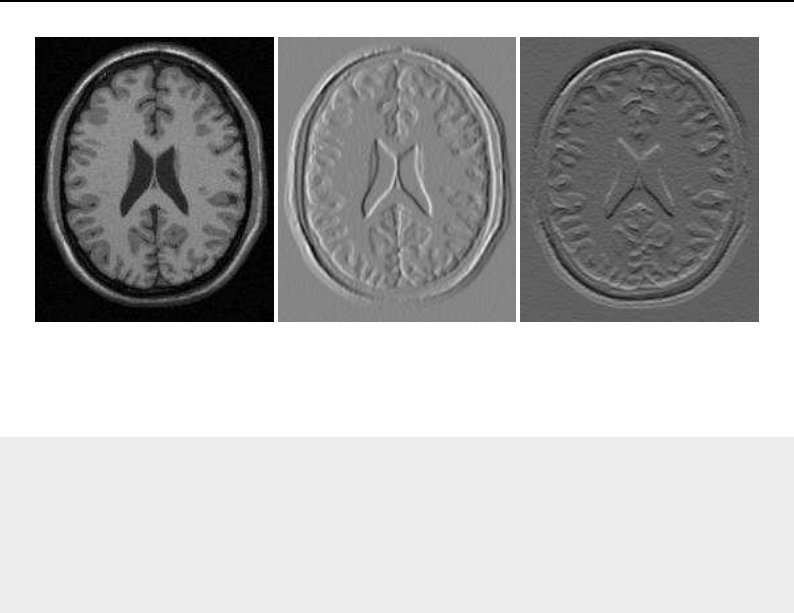

The National Library of Medicine Insight Segmentation and Registration Toolkit, shortened as the

Insight Toolkit (ITK), is an open-source software toolkit for performing registration and segmenta-

tion. Segmentation is the process of identifying and classifying data found in a digitally sampled

representation. Typically the sampled representation is an image acquired from such medical instru-

mentation as CT or MRI scanners. Registration is the task of aligning or developing correspondences

between data. For example, in the medical environment, a CT scan may be aligned with a MRI scan

in order to combine the information contained in both.